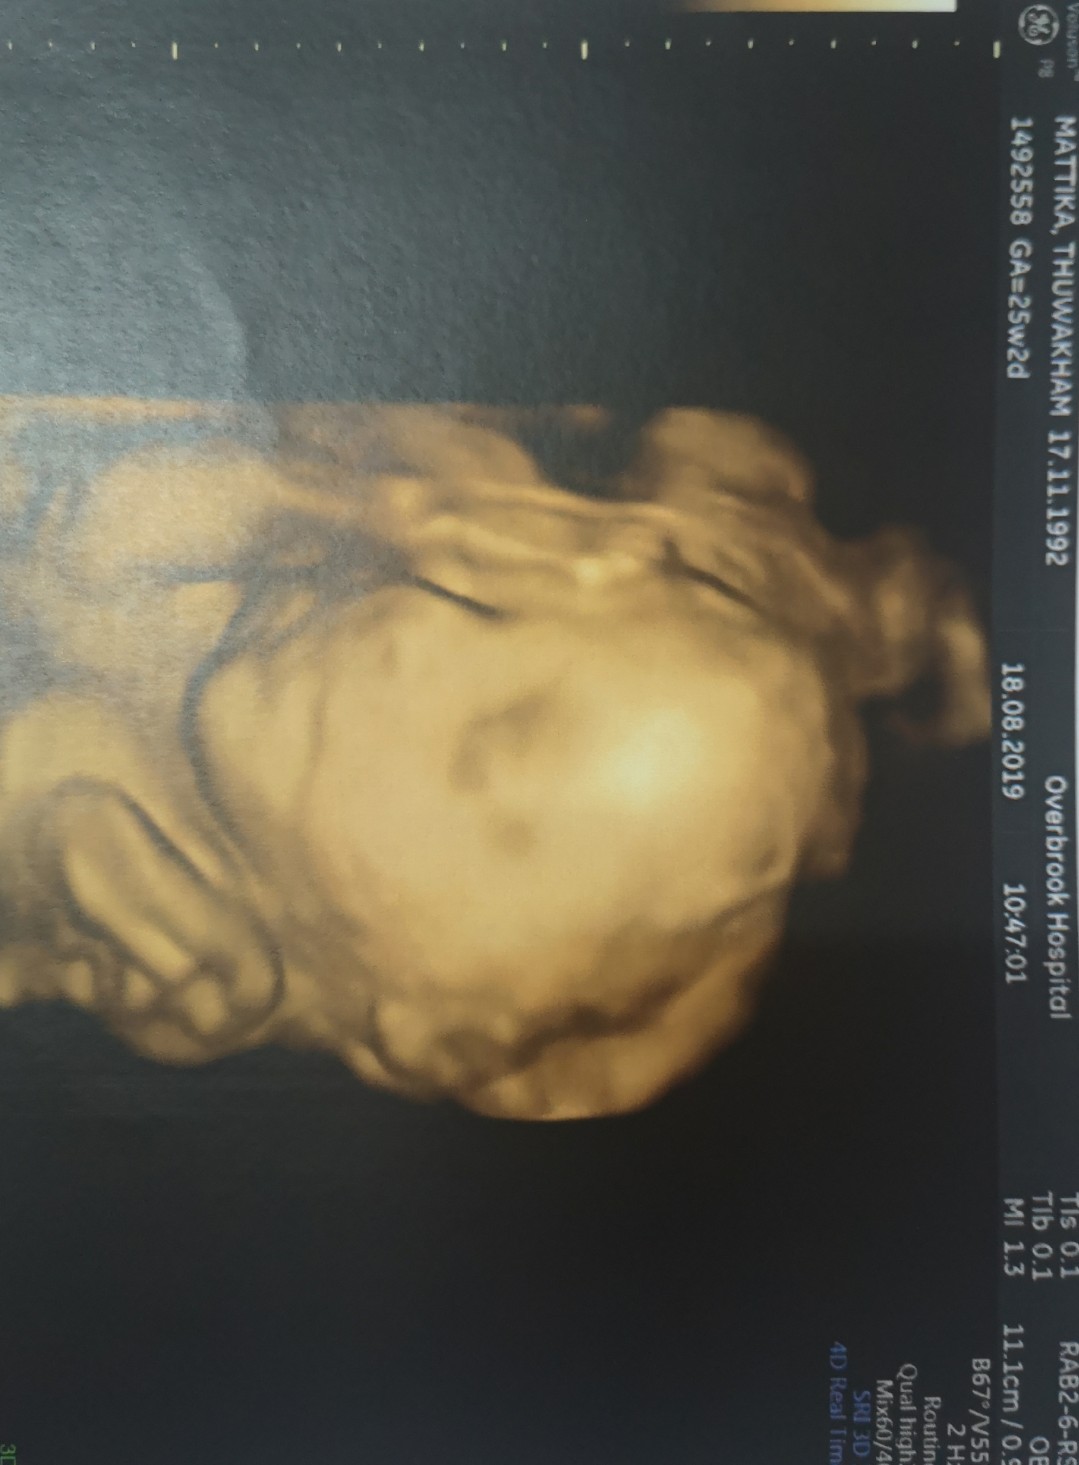

รูปนี้ซาวด์ตอน 25 วีคค่า ปัจจุบันนี้ 30+5 แล้ว กำหนดคลอด 29 พ.ย. ค่า